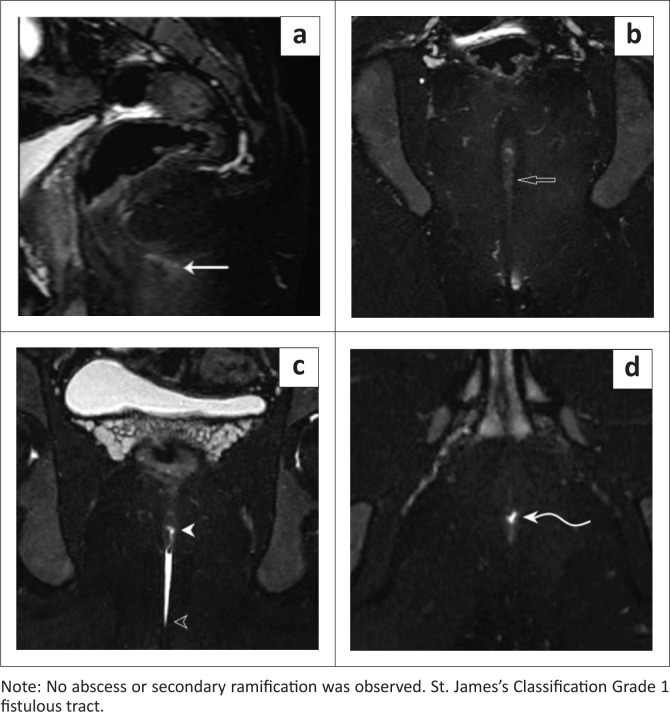

Background: Magnetic resonance fistulography (MRF) is a key non-invasive imaging technique for mapping perianal fistulas before surgery. The instillation of aqueous jelly, like ultrasound gel, enhances the signal-to-noise ratio, improving image quality and MRF accuracy. This low-cost approach improves accessibility, especially in resource-limited settings, while ensuring patient comfort and safety.

Objectives: To determine the impact of aqueous jelly on the accuracy of MRF in identifying fistulous tracts, internal openings, secondary ramifications and abscesses and the quality of visualisation of MRF with and without jelly instillation.

Method: A cross-sectional study at Krishna Rajendra and Cheluvamba Hospitals, Mysore (October 2024-March 2025), included 40 patients with perianal fistulas. Magnetic resonance fistulography was performed using a 1.5 Tesla uMR 570 system, without and with 5 mL - 7 mL of sterile aqueous jelly instilled percutaneously. MRI findings were compared with intraoperative results. Data were analysed using Statistical Package for the Social Sciences (SPSS) to assess sensitivity, specificity and accuracy.

Results: Magnetic resonance fistulography with gel improved visualisation, identifying internal openings in 92.5% of cases (vs. 24% without gel) and secondary tracts in 40% (vs. 17.5%). The accuracy compared to surgery was 97.5% for internal openings, 95% for secondary tracts, 97.5% for abscesses and 100% for supralevator extension.

Conclusion: Aqueous jelly instillation enhances MRF accuracy, improving fistula visualisation and aiding in preoperative planning. This technique reduces recurrence and incontinence risk and supports more accurate surgical interventions.